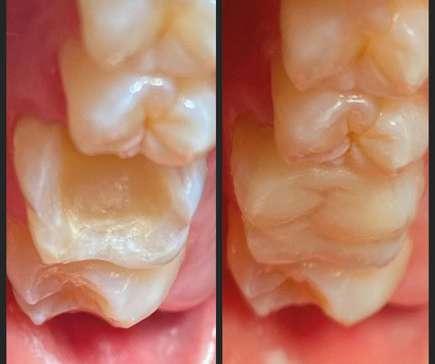

Caso clínico

Presentamos el caso de un paciente masculino de 61 años de edad, bruxista, con evidentes desgastes en toda la dentición y cracks de esmalte que pueden observarse en las fotografías iniciales de la primera visita (figuras 1 y 2). En las fotografías

Figuras 1 y 2. Imágenes intraorales de la primera visita donde se hacen evidentes diferentes desgastes en los dientes anteriores y a mayor detalle crakcs en el esmalte, así como lesiones por abfracción en los cuellos de los dientes de los premolares y caninos superiores.

laterales se ponen de manifiesto aún más varias lesiones de esmalte que indican la parafunción en el paciente, unido a los desgastes excesivos en varias zonas (figuras 3 y 4). El paciente acude por dolor y movilidad en la pieza 11, que se ha incrementado en los últimos días, además de sensación de “diente crecido” que como podemos ver en las fotografías iniciales es real, ya que el diente se encuentra ligeramente extruido en relación con el contralateral. Estos signos parecen indicarnos una fractura o fisura. En la fotografía oclusal, podemos observar el desplazamiento del diente debido a la movilidad (figura 5). Posteriormente se realiza un sondaje positivo de la pieza, que lleva a 11 mm por lo que se confirma la sospecha de fractura y se procede a la exodoncia del diente, realizándose una regeneración posterior del alveolo con PRGF-Endoret y

Figuras 3 y 4. Fotografías laterales donde se evidencian los cracks de esmalte en varios dientes y los desgastes excesivos en varios puntos. En estas imágenes se hacen más evidentes las lesiones por abfracción.